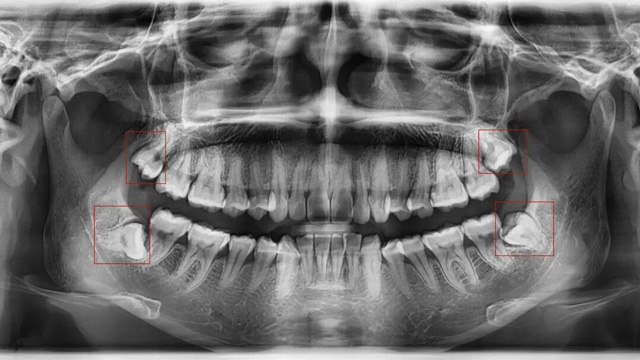

这是最常见的拔除原因。正畸的核心需求之一一般是“排齐拥挤牙齿”,而智齿作为口腔中最后萌出的牙齿(通常在20岁左右萌出),由于生长位置特殊、空间有限,很可能会持续挤压旁边的第二磨牙,导致第二磨牙倾斜、移位,进而引发整个牙列拥挤。

如果通过X光片发现,你的智齿已经顶到邻牙牙根,或者导致邻牙出现龋坏、牙周炎,无论是否正畸,都建议尽早拔除。

有些智齿虽然目前没有疼痛、没有挤压邻牙,但拍X光片后发现,它属于“埋伏阻生”(完全埋在牙龈下),或者生长方向异常,未来很可能会萌出、挤压邻牙,甚至引发囊肿、肿瘤等问题。对于这类堪比“定时炸弹”的智齿,医生通常会建议拔除,避免后续出现更严重的口腔问题。